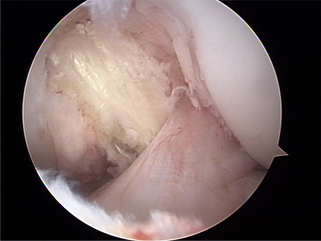

후방십자인대 재건후